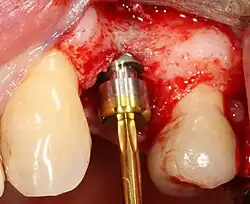

- Placement of the implant: The implant screw is placed and can be self-tapping;[50]: 100–102 otherwise, the prepared site is tapped with an implant analog. It is then screwed into place with a torque controlled wrench[54] at a precise torque so as not to overload the surrounding bone (overloaded bone can die, a condition called osteonecrosis, which may lead to failure of the implant to fully integrate or bond with the jawbone).

- Tissue adaptation: The gingiva is adapted around the entire implant to provide a thick band of healthy tissue around the healing abutment. In contrast, an implant can be "buried", where the top of the implant is sealed with a cover screw and the tissue is closed to completely cover it. A second procedure would then be required to uncover the implant at a later date.